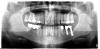

Paul Опубликовано 15 августа, 2011 Поделиться Опубликовано 15 августа, 2011 Здравствуйте, Продолжая тему об имплантатах с памятью формы.Сегодня был у меня пациент. Из анамнеза в 2000 году поставили 2 имплантата, причем один имплантат со слов пациента "долго не приживался" были боли, чувство онемения подбородка не было. затем со слов пациента ему убрали имплантат и поставили на его место другой. потом вроде все прошло и вот он пришел ко мне через 11 лет с жалобами на дискомфорт при приеме пищи и подвижность всей конструкции. Я сделал ему ОПТГ. Получается что ему установили 2 имплантата одной фирмы в начале, потом всвязи с отсутствием остеоинтеграции удалили дальний имплантат и поставили с памятью формы и взяли все блоком. Снимок прилагаю. Считаю что просто ближний имплантат держал всю конструкцию. В полости рта у дальнего имплантата все в разрастаниях грануляционной ткани подвижность 3 степени. Ссылка на комментарий

kriokov Опубликовано 15 августа, 2011 Поделиться Опубликовано 15 августа, 2011 Снимок прилагаю. Считаю что просто ближний имплантат держал всю конструкцию. В полости рта у дальнего имплантата все в разрастаниях грануляционной ткани подвижность 3 степени.с дистальной опорой все понятно, а вот, что за медиальная опора не совсем понял. На снимке она не однородная какая то по структуре. Если удалять будете сфоткайте. Ссылка на комментарий

Paul Опубликовано 16 августа, 2011 Поделиться Опубликовано 16 августа, 2011 Ближний имплантат не знаю какой фирмы, но я такие удалял. верхняя половина как правило уже сломана и держится незначительно винтом. при удалении подвиной супраструктуры она ломается от внутри костной части и мне приходилось ее выпиливать блоком. Ссылка на комментарий